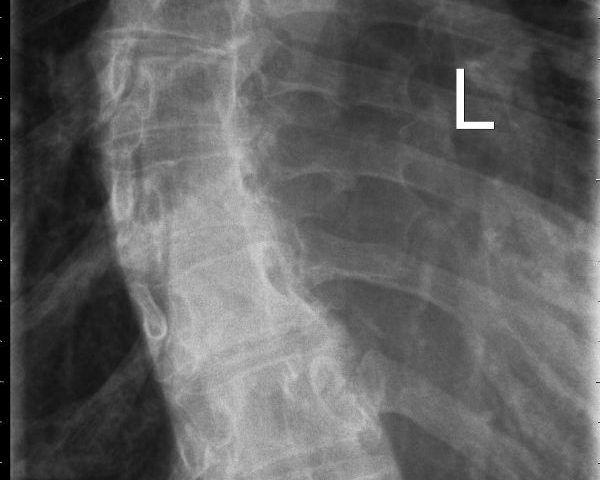

وتتمثل أعراض هذا التشوه العظمي في انحناء العمود الفقري واستدارة الفقرات، وفي بعض الأحيان يتخذ العمود الفقري شكل حرف S أو حرف C، بالإضافة إلى عدم استواء الكتفين وميل الحوض.

وشدد فليشتنماخر على ضرورة عرض الطفل على طبيب عظام في أسرع وقت ممكن، مشيراً إلى أنه يمكن الاستدلال على انحراف العمود الفقري من خلال الأشعة السينية.